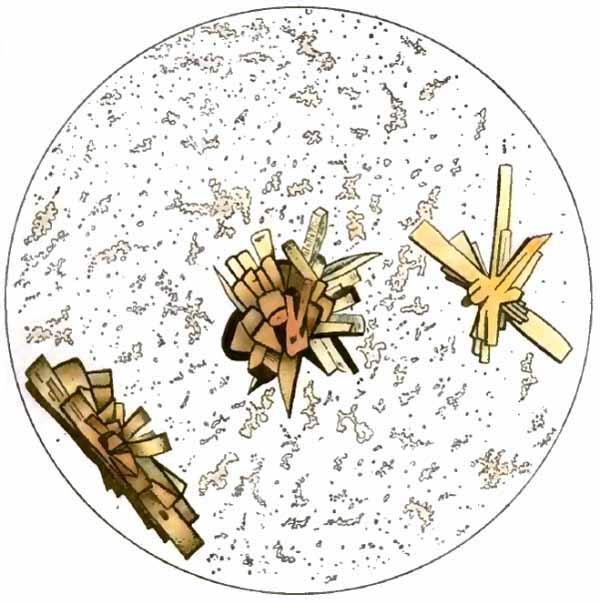

Charcot-Leyden crystals

FIG. 6.—Charcot-Leyden crystals (after Riegel).

[p. 30] 3. Charcot-Leyden Crystals.—Of the crystals which may be found in the sputum, the most interesting are the Charcot-Leyden crystals. They are rarely found except in cases of bronchial asthma, and were at one time thought to be the cause of the disease. They frequently adhere to Curschmann spirals. Their exact nature is unknown.

They are colorless, pointed, often needle-like, octahedral crystals (Fig. 6). Their size varies greatly, the average length being about three or four times the diameter of a red blood-corpuscle.

Other crystals—hematoidin, cholesterin, and, most frequently, fat needles—are common in sputum which has remained in the body for a considerable time.